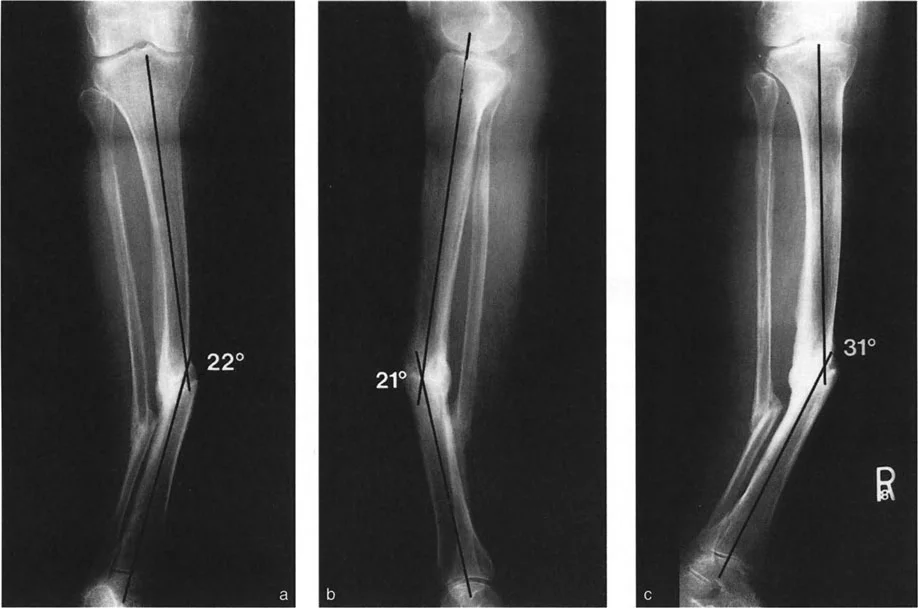

- الأشعة مع تحمل الوزن (Weight-bearing X-rays): تُظهر كيف تتصرف المفاصل والعظام تحت الضغط الطبيعي للجسم، وهو أمر حيوي لتقييم التشوهات الديناميكية.

- أشعة الأطراف الطويلة (Long Leg Films): تُؤخذ هذه الأشعة من الورك إلى الكاحل في صورة واحدة لتقييم المحور الميكانيكي الكامل للطرف السفلي وتحديد أي انحرافات.

- التصوير المقطعي المحوسب (CT Scans): يوفر صورًا ثلاثية الأبعاد للعظام، وهو مفيد بشكل خاص لتقييم التشوهات الالتوائية (مثل الورم الفخذي المفرط) وتحديد موقع مركز دوران الانحراف (CORA) بدقة.